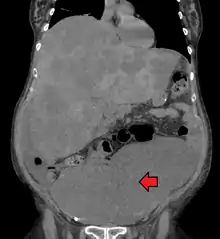

Medical imaging

A colorectal cancer is sometimes initially discovered on CT scan.

Presence of metastases is determined by a CT scan of the chest, abdomen and pelvis.[18] Other potential imaging tests such as PET and MRI may be used in certain cases.[18] The latter is often used for rectal lesions to determine its local stage and to facilitate preoperative planning.